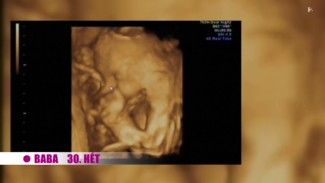

A terhesség 30. hete

A Babapercek adásából kiderült, mennyire kifinomultak a harminc hetes babák érzékszervei, valamint azt, mely vitaminok elengedhetetlenek a babák egészséges fejlődéséhez.